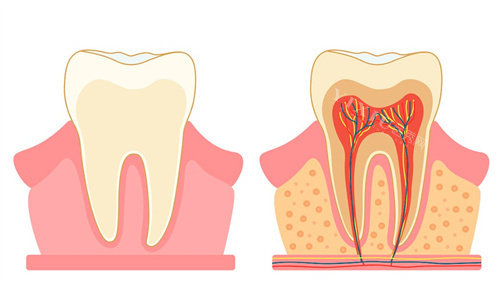

医院在儿童口腔疾病的治疗上,有着可靠的医生和设备,能处理像儿童牙齿外伤、急性牙髓炎等急诊情况 。